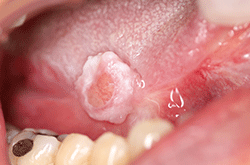

図❷ 約10年後の右舌縁の所見

現病歴:いつからかは不明であるが、歯や床義歯が右舌縁と接触して痛みを自覚したため、近歯科医院にて調整を行っていたが改善なく、当科を受診(図❶)。細胞診を施行し、ClassIIIの結果で生検を行った。その結果、扁平上皮がん(以下、SCC)の報告があり、2006年5月、右舌がん切除術を施行した。その後、外来にて定期的な経過観察を行った。2017年11月、右舌縁に白色病変を伴った潰瘍を認め(図❷)、生検にてSCCの報告があり、再度舌部分切除術を施行した。以後、経過良好のため外来にて経過観察を行うも、2018年2月、腫瘍切除部位に有茎性の腫瘤を認めた(図❸)。

口腔内所見:右舌縁に、約10mmの有茎性の腫瘤を認めた。腫瘤は充実性で表面滑沢、潰瘍-、出血-、易出血性-、腫瘤周囲に白色病変+、腫瘤周囲組織の硬結±、であった。